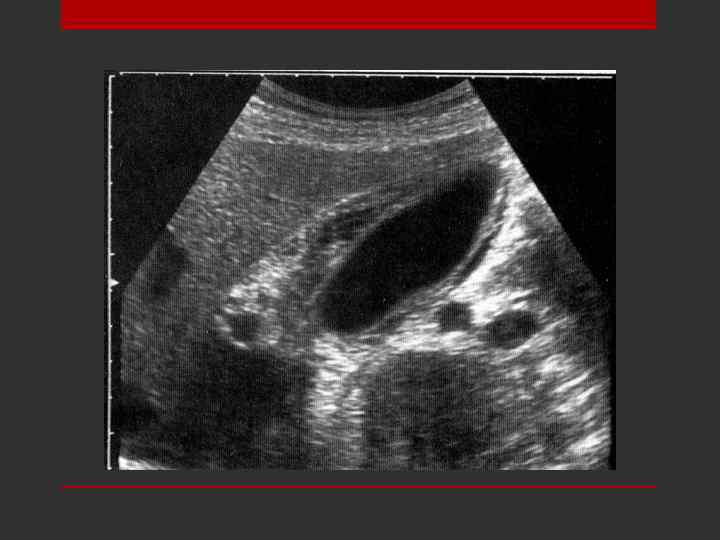

Острый лимфаденит (лимфатический узел в средней трети шеи слева кнаружи от сосудистого пучка у больного с тромбозом яремной вены). Неровное, округлое, гиперэхогенное образование в центре. Вокруг анэхогенное округлое образования с нечеткими краями. Капсула четко не дифференцируется.